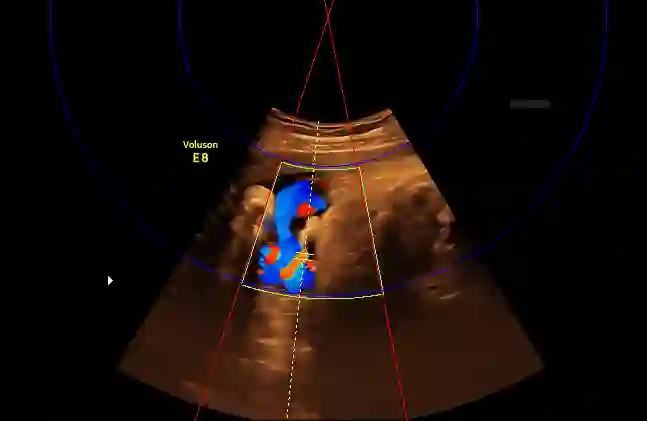

Examination of the umbilical artery with Doppler ultrasonography is performed to investigate blood supply to the fetus through the umbilical cord, which is vital for the monitoring of fetal health. Such examination involves several steps that must be performed correctly: identifying suitable sites on the umbilical artery for the measurement, acquiring the blood flow curve in the form of a Doppler spectrum, and ensuring compliance to a set of quality standards. These steps rely heavily on the operator's skill, and the shortage of experienced sonographers has thus created a demand for machine assistance. In this work, we propose an automatic system to fill the gap. By using a modified Faster R-CNN network, we obtain an algorithm that can suggest locations suitable for Doppler measurement. Meanwhile, we have also developed a method for assessment of the Doppler spectrum's quality. The proposed system is validated on 657 images from a national ultrasound screening database, with results demonstrating its potential as a guidance system.